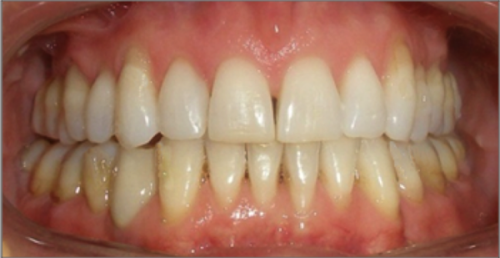

44 year old female:

Diagnosis:

- Upper and lower arch collapse due to missing teeth

- Retrusive angulation of upper & lower front teeth

- Severe collision and wear of front teeth

Treatment:

- Combination of Invisalign and braces

- Creating space for placement of an implant in the lower arch

- 28 months